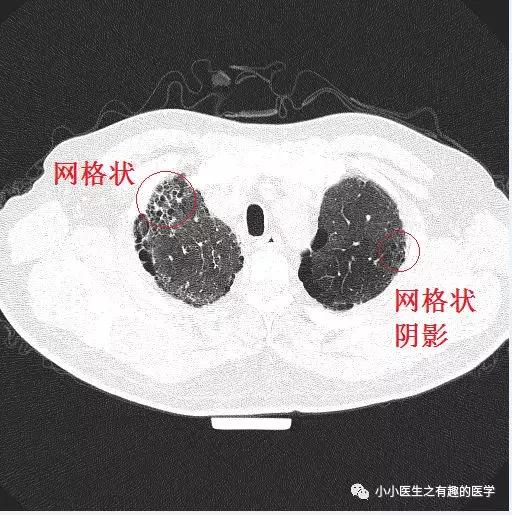

经典的间质性肺炎,就是一张网!

1.胸膜下2.网格状很多间质性肺炎,都有这个特征,是间质性肺炎的入门知识,也是很重要的知识。